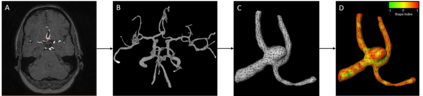

The growth of unruptured intracranial aneurysms (UIAs) is a predictor of rupture. Therefore, for further imaging surveillance and treatment planning, it is important to be able to predict if an UIA is likely to grow based on an initial baseline Time-of-Flight MRA (TOF-MRA). It is known that the size and shape of UIAs are predictors of aneurysm growth and/or rupture. We perform a feasibility study of using a mesh convolutional neural network for future UIA growth prediction from baseline TOF-MRAs. We include 151 TOF-MRAs, with 169 UIAs where 49 UIAs were classified as growing and 120 as stable, based on the clinical definition of growth (>1 mm increase in size in follow-up scan). UIAs were segmented from TOF-MRAs and meshes were automatically generated. We investigate the input of both UIA mesh only and region-of-interest (ROI) meshes including UIA and surrounding parent vessels. We develop a classification model to predict UIAs that will grow or remain stable. The model consisted of a mesh convolutional neural network including additional novel input edge features of shape index and curvedness which describe the surface topology. It was investigated if input edge mid-point co-ordinates influenced the model performance. The model with highest AUC (63.8%) for growth prediction was using UIA meshes with input edge mid-point co-ordinate features (average F1 score = 62.3%, accuracy = 66.9%, sensitivity = 57.3%, specificity = 70.8%). We present a future UIA growth prediction model based on a mesh convolutional neural network with promising results.